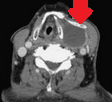

Thyroglossal duct cysts. Neck MRI – Detailed imaging of the cyst. Courtesy Dr. V. Penopoulos.